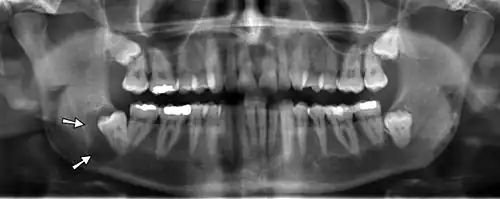

Panoramic radiograph

A dental panoramic radiograph, showing the maxilla and mandible, all the teeth including the "wisdom teeth," the frontal and maxillary sinuses, the nasal cavity and the temporomandibular joint and other near by head and neck anatomy. | |

A panoramic radiograph is a panoramic scanning dental X-ray of the upper and lower jaw. It shows a two-dimensional view of a half-circle from ear to ear. Panoramic radiography is a form of focal plane tomography; thus, images of multiple planes are taken to make up the composite panoramic image, where the maxilla and mandible are in the focal trough and the structures that are superficial and deep to the trough are blurred.